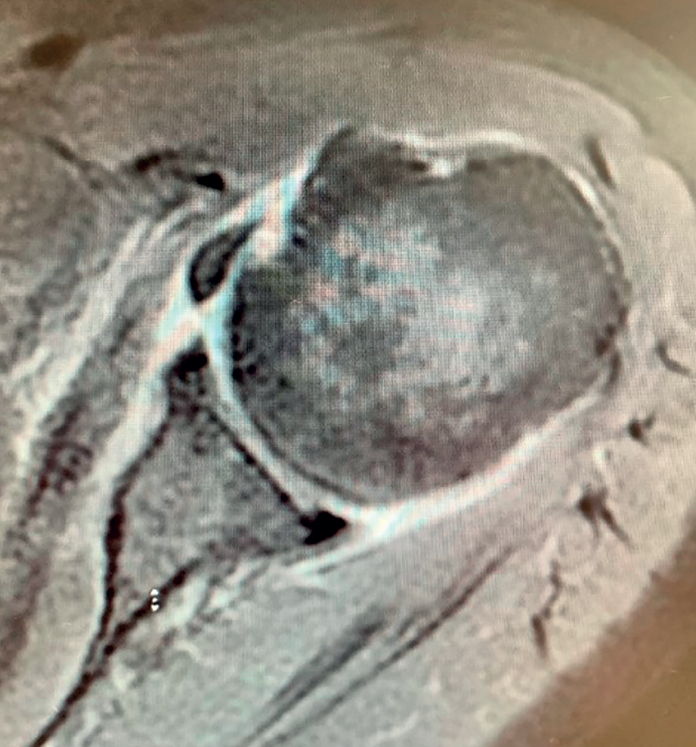

Boileau in 2005 or Simovitch in 2007(28,32) concluded that reverse replacement is unable to secure the restoration of external rotation. In many patients, only the teres minor will be able to afford active external rotation. If the teres minor presents rupture, retraction or adipose degeneration (which can be assessed by magnetic resonance imaging or computed tomography), we can predict a poorer outcome in these individuals, with an external rotation deficit(33,34). The lack of external rotation may prove quite disabling, especially in patients that use the arm in abduction. For this reason, some investigators such as Longo, in 2011(35), indicate the possibility of latissimus dorsi transfer to the reverse replacement implant, to restore external rotation in the patient.